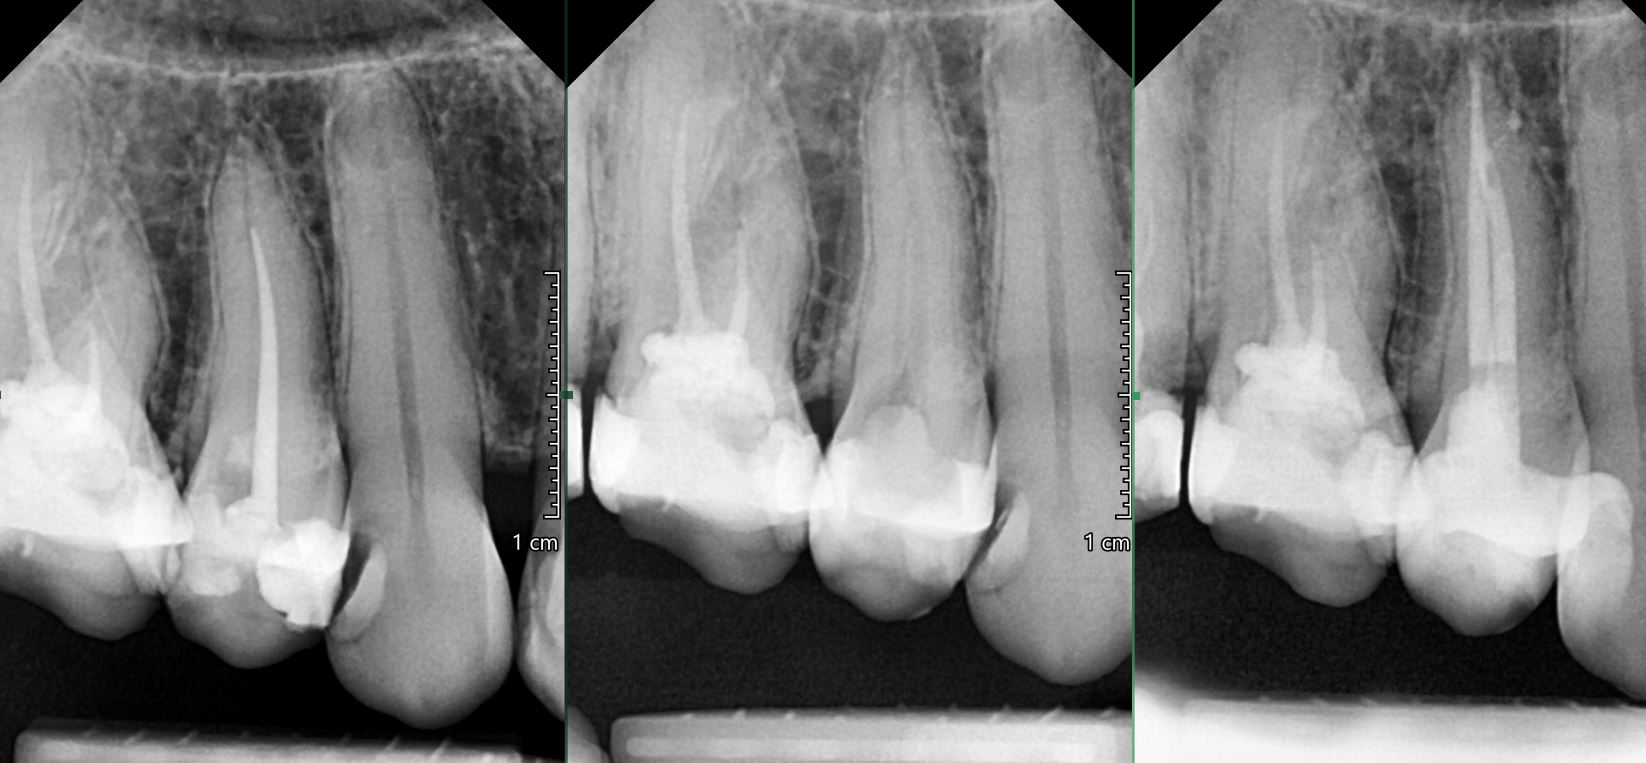

OŠETŘENÍ PACIENTŮ POD OPERAČNÍM MIKROSKOPEM

Nabízíme možnost delegovat Vaše pacienty k (re)endodontickému ošetření pod operačním mikroskopem.